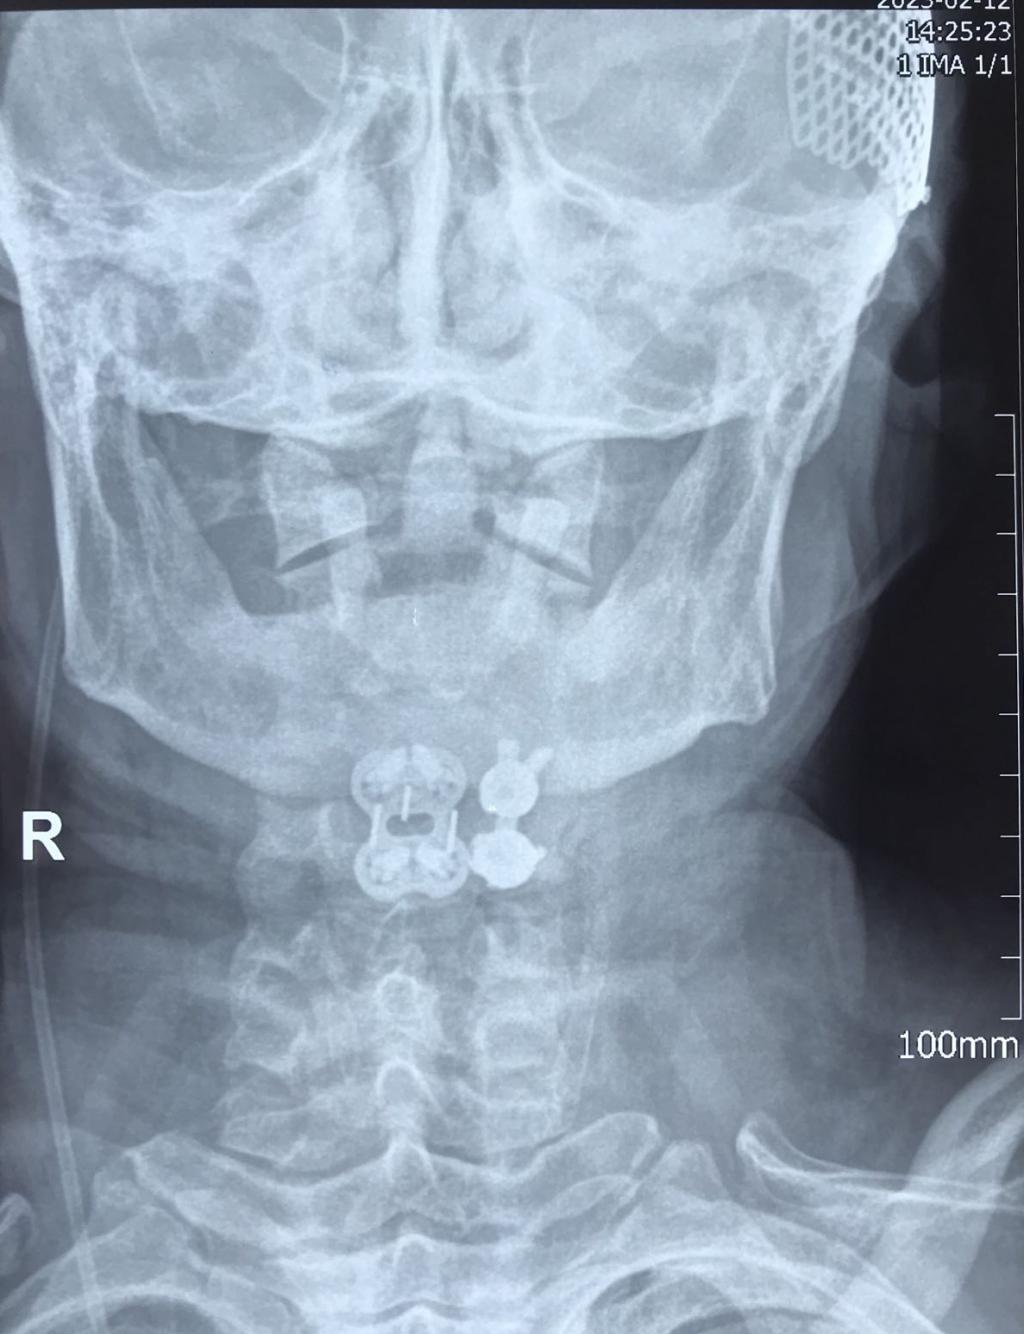

经过有序准备,为患者先行颈后路减压,解锁关节突绞索,牵引复位,使用颈椎侧块螺钉固定,同时椎板间植骨融合。随后再将患者转为仰卧位,再行颈前路脱位椎体的间盘摘除,融合器植入,钢板螺钉固定,历时3小时,顺利结束。患者术后恢复良好,肢体功能状态较术前改善显著,上肢抽痛症状消失,肌力已达4-5级,患者及家属对治疗效果颇为满意。